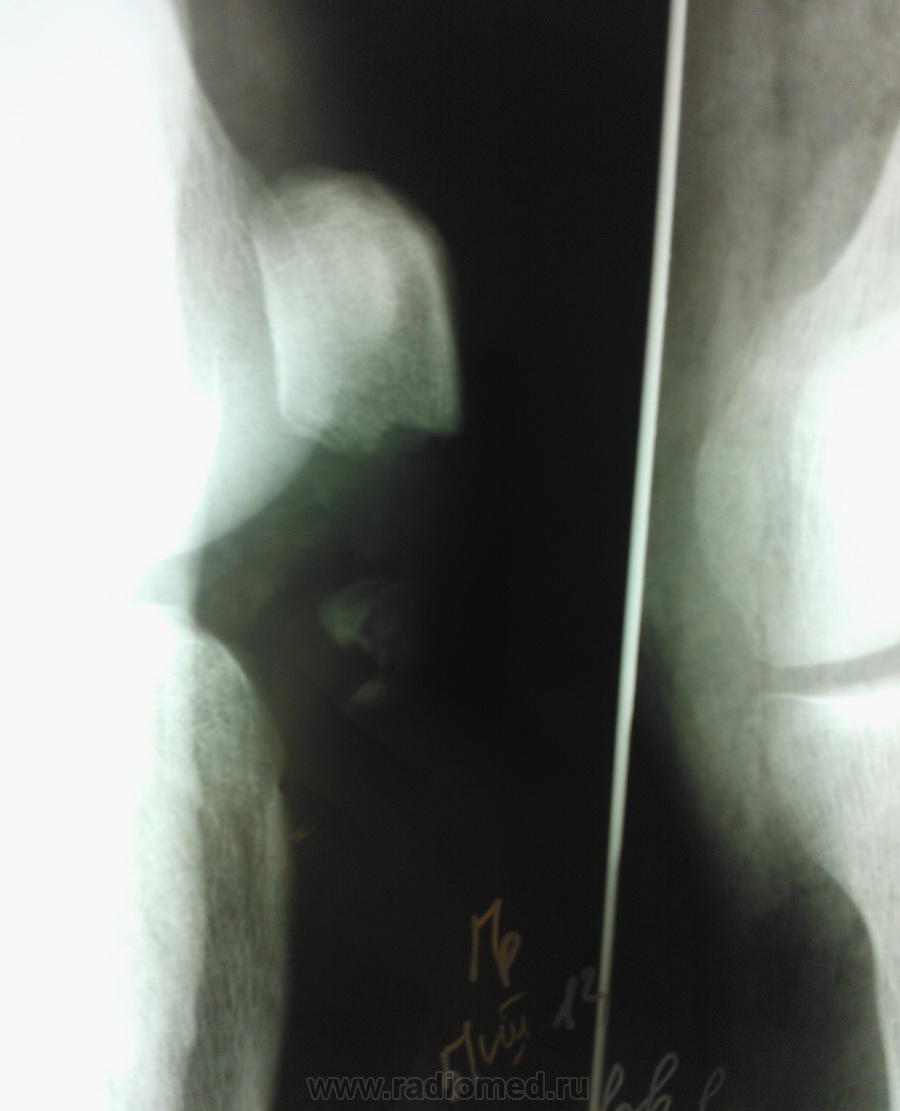

добавил рентгенограмму, сегодня сделали контрольный снимок в гипсе, видимо оперировать передумали.

Да и голень разгибаться не будет. Скажите хирургам, пусть не выдумывают.

Уважаемый рентгенолог без опыта работы, существует несколько локализаций переломов, консервативное лечение которых малоэффективно. Например, переломы надколенника, локтевого отростка, шейки бедра со смещением. Их нужно оперировать, даже если очень не хочется. Потом будет ещё хуже. Если Ваши хирурги тоже без опыта работы, пожалуйста, передайте им эту информацию. Пусть не инвалидизируют пациентов.